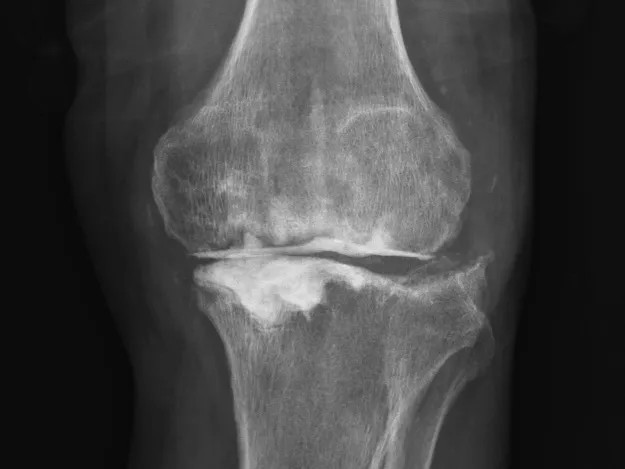

68岁的张先生(化名),本以为一次膝关节单髁置换手术能终结他的疼痛。然而,术后感染不期而至,将他的生活拖入长达8个月的灰暗期。

膝关节持续红肿、疼痛,每一步都伴随着不适与恐惧。反复治疗,效果却不尽如人意。传统手段面对此类术后感染、结构遭破坏的复杂局面,往往力不从心,患者可能需要经历多次手术,且功能恢复难以保障。

清创只是第一步,如何在一片“复杂地形”中重建一个稳定、功能良好的膝关节,是更大的挑战。为此,团队引入了计算机辅助手术规划系统。

通过患者的CT数据,系统构建出膝关节的三维数字模型,精确评估骨缺损的范围与形态。医生可以在虚拟空间中,提前模拟手术过程,为患者“量体裁衣”,规划出假体安放的最佳位置、角度以及所需填充骨缺损的特殊垫块型号。